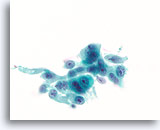

Atypische proliferatieve ductale laesie, Borst FNA, ThinPrep®.

Let op de duidelijke celstratificatie. In het midden is duidelijk een vaag stromingspatroon zichtbaar, wat pleit voor benigne ductale hyperplasie, maar als de architecturele ordening van de cellen niet gekarakteriseerd kan worden, kan atypische ductale hyperplasie niet worden uitgesloten.

Atypische proliferatieve ductale laesie, Borst FNA, ThinPrep®.

Let op de duidelijke celstratificatie. In het midden is duidelijk een vaag stromingspatroon zichtbaar, wat pleit voor benigne ductale hyperplasie, maar als de architecturele ordening van de cellen niet gekarakteriseerd kan worden, kan atypische ductale hyperplasie niet worden uitgesloten.